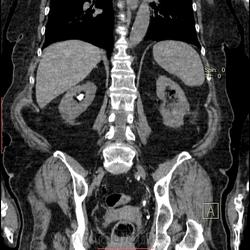

Случай 2.

Женщина. Колика справа. До этого 4 оперативных вмешательства по поводу МКБ. По данным КТ за декабрь 2012 года камень в правой почке.

По данным в\в урографии на сегодня